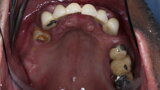

Compromised maxillary dentition treated with Straumann Pro Arch and a digital workflow